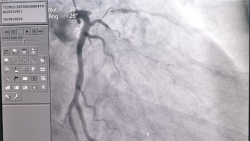

Sau một lần đi khám sức khỏe định kỳ tại Bệnh viện 108, người đàn ông hút thuốc lá lâu năm phát hiện bản thân bị hẹp khít mạn tính động mạch vành.

Mới đây, các bác sĩ Bệnh viện Nhân dân 115 (TP.HCM) vừa cấp cứu cho nam bệnh nhân bị nhồi máu cơ tim cấp khi chỉ mới 25 tuổi.